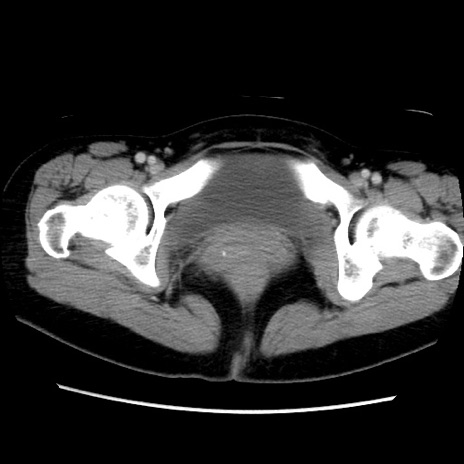

症例39(横断像)

【症例】40歳代女性

【主訴】上下腹部痛

【現病歴】2日目から下腹部痛あり。夜間は痛みで眠れなかった。昨日より上腹部痛と下痢が出現。臥位で痛みは軽快したため、休んでいた。本日になって臥位でも立位でも痛みが強くなってきたため救急要請。

【既往歴】子宮内膜症

【身体所見】部:平坦・軟、左上下腹部に圧痛あり、反跳痛あり。

【データ】WBC 21800、CRP 26.78